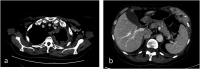

Background: Malignant pleural mesothelioma is the most common primary tumor of the pleura. The unique growth pattern of malignant pleural mesothelioma makes it difficult to apply the Response Evaluation Criteria for Solid Tumors (RECIST). Hence the need to use modified RECIST (mRECIST) criteria, as they better fit the unique growth pattern of malignant pleural mesothelioma. The thickness of the tumor perpendicular to the chest wall or mediastinum is measured at 2 points at 3 separate levels at least 1 cm apart on chest CT scans, and summed to obtain a one-dimensional pleural measurement. The same criterion has also been used to assess response to treatment. RECIST 1.1 represents a further update, taking into account new concepts such as revised minimum dimensions for lymph nodes and an approach to lesions that become non-measurable. Based on experience and published literature, the hypothesis of merging the 2 above-mentioned criteria in mRECIST 1.1 for mesothelioma and the use of iRECIST for the application to immune-based therapies (iRECIST) was considered. Purpose: Support the importance of studying pleural mesothelioma in a reliable and reproducible way, through a scrupulous methodology, applying the mRECIST1.1 and iRECIST criteria. Conclusions: Adoption of a standardized study metodology can make the study of PM reproducible and correct.